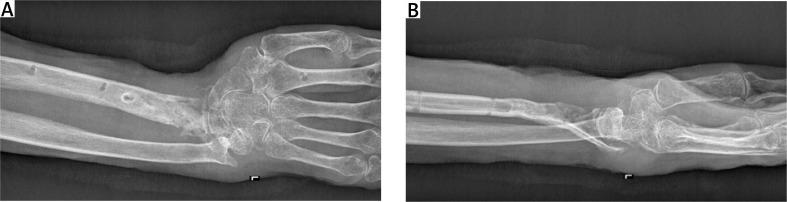

An aggressive course of pyoderma gangrenosum mimicking bacterial osteomyelitis after open reduction and internal fixation of a distal radius fracture with a titanium plate.

Pyoderma gangrenosum (PG) is a rare condition characterized by the development of aseptic, non-healing skin ulcers. Any skin trauma, such as a surgical incision, can trigger an outbreak of lesions. Our case and literature review show that a physician should consider PG in every event of a non-healing, aseptic wound after surgery. The treatment of PG requires collaboration within a multidisciplinary team and immunosuppressive therapy is the first line of treatment, while surgical interventions should be avoided in the active stage of PG.